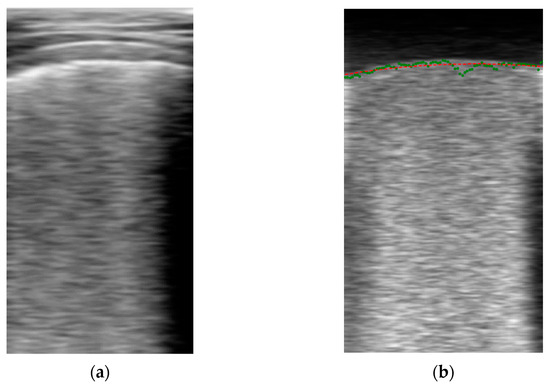

Pre-Processing Block